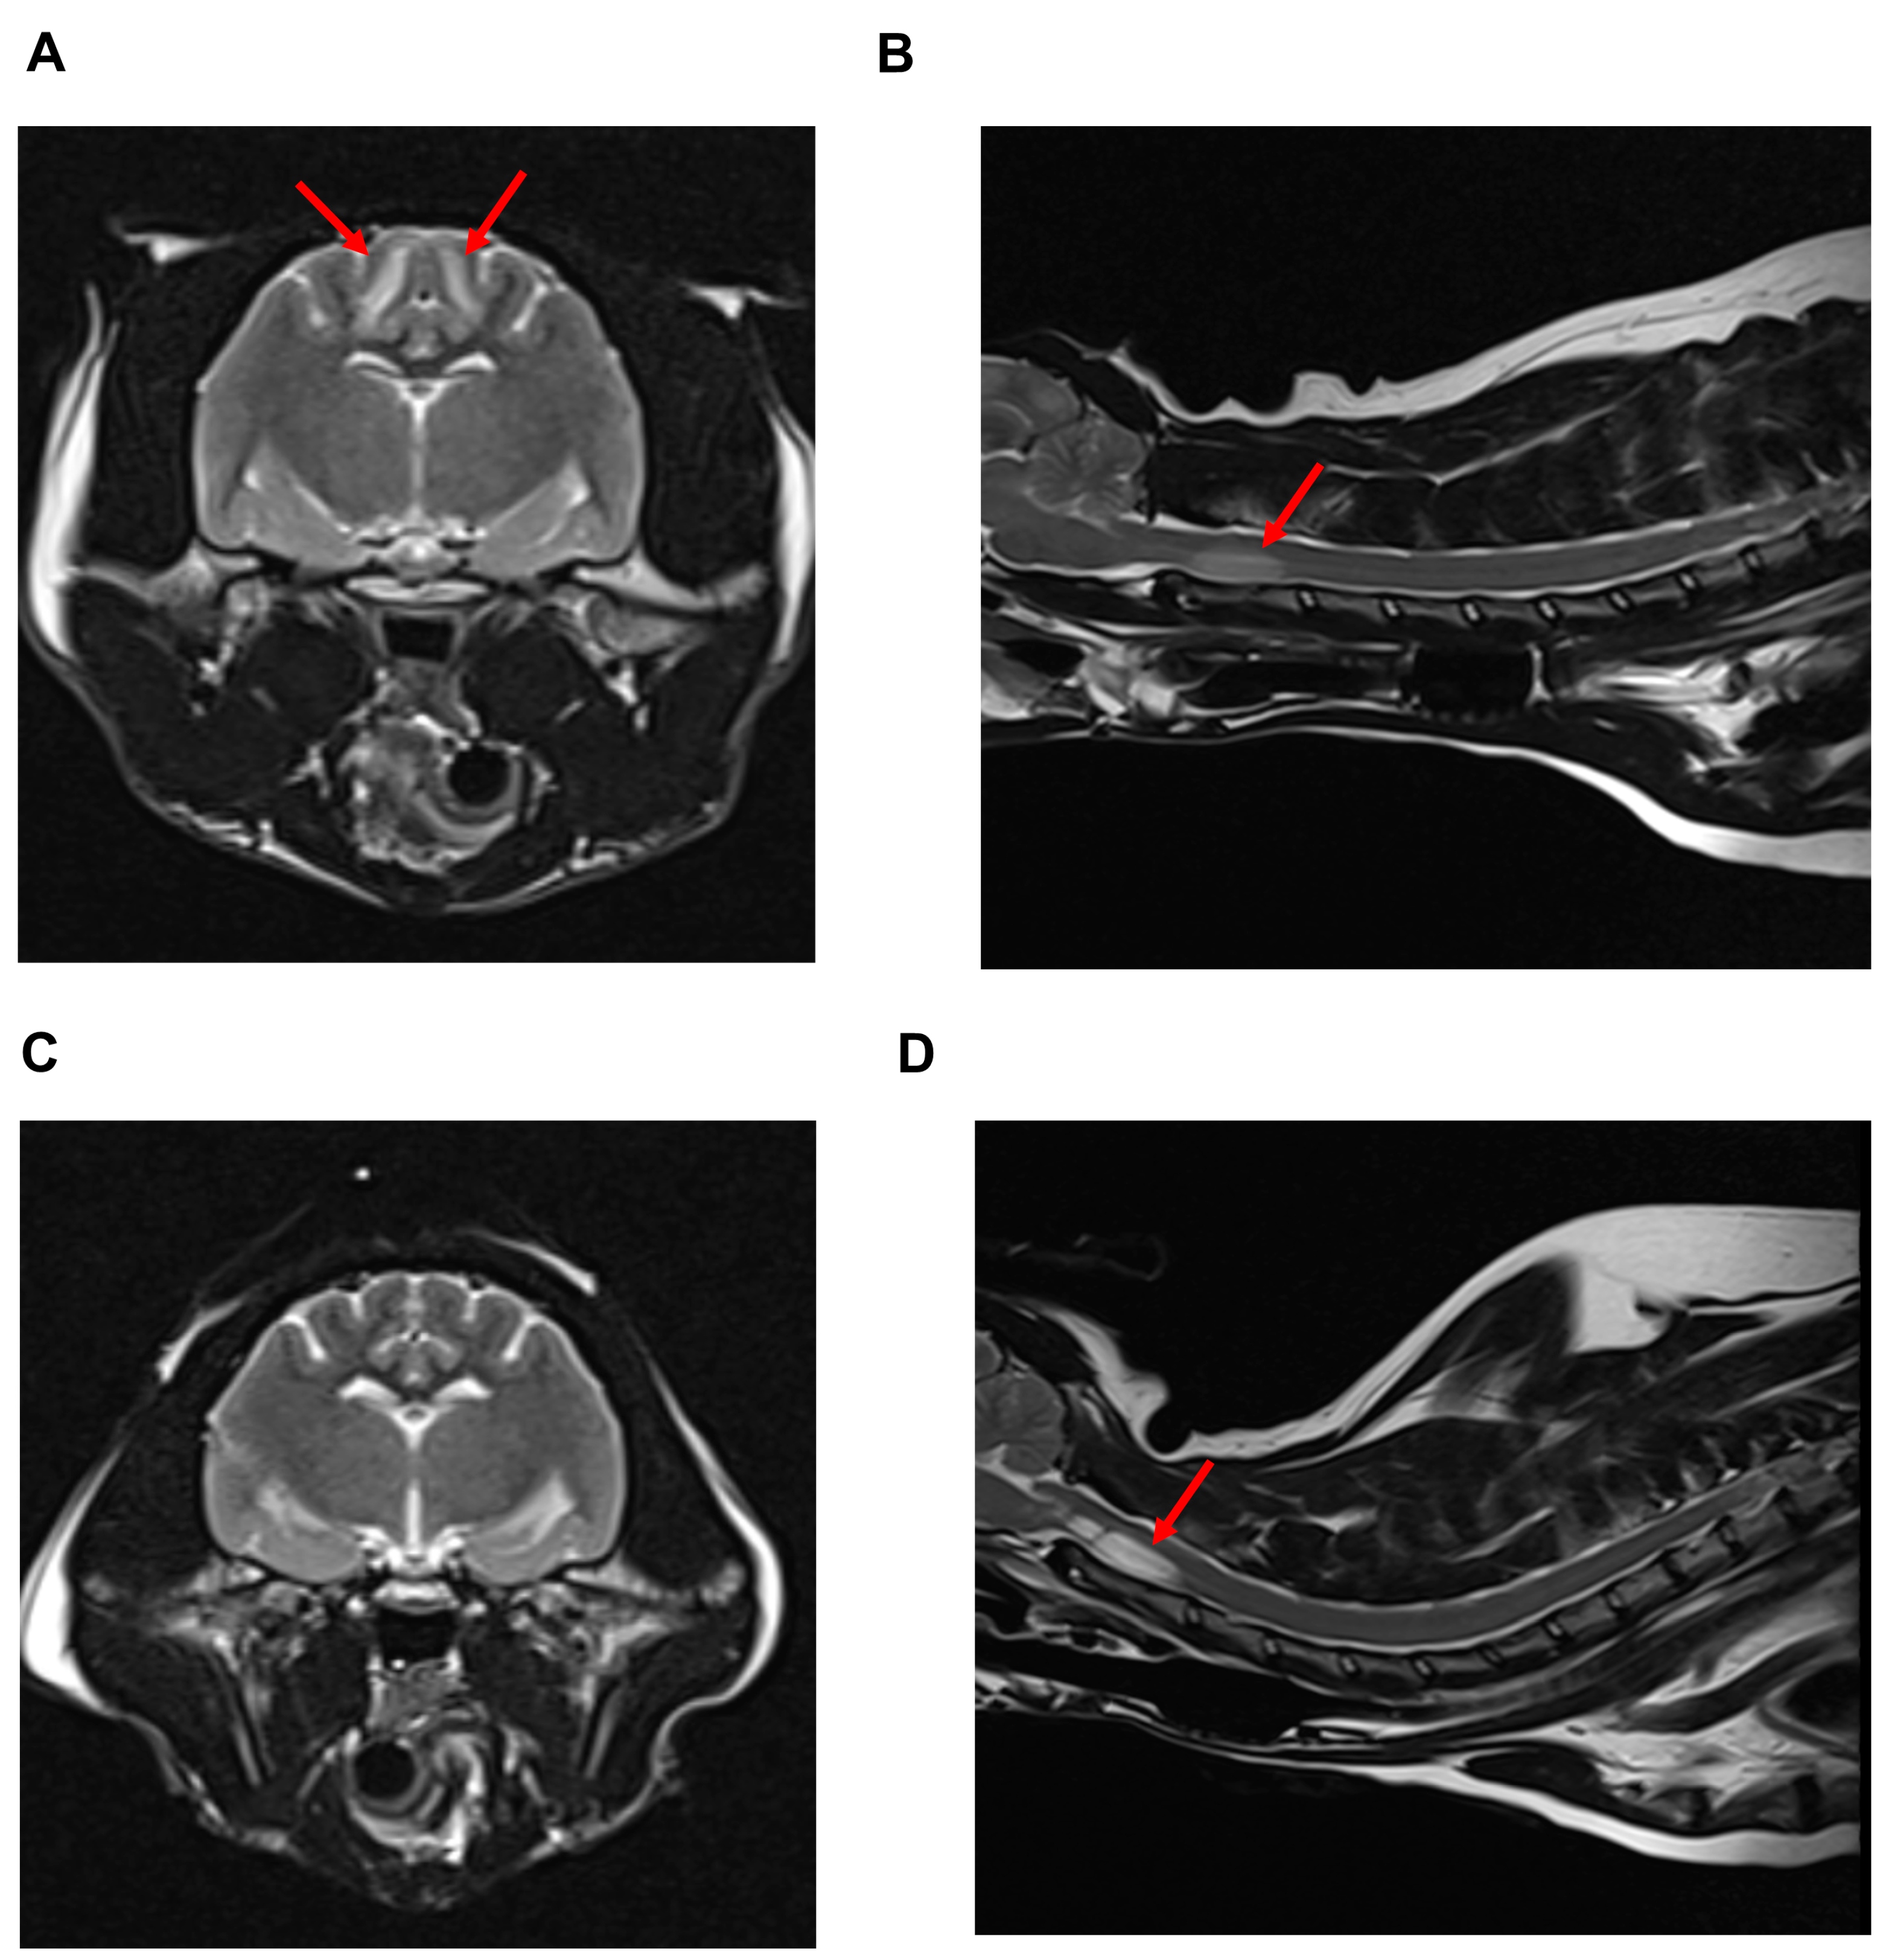

2. Case Description